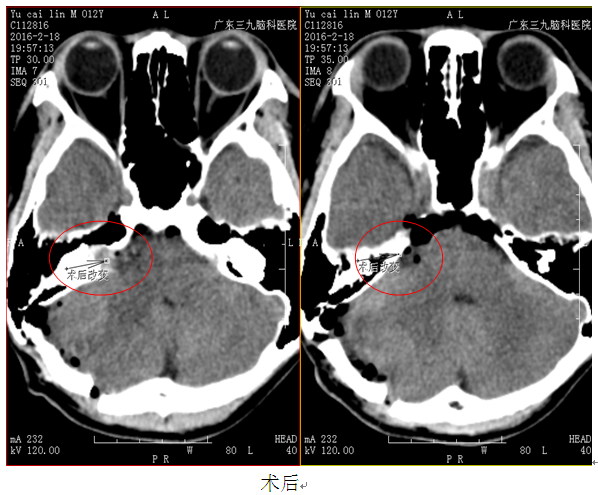

入院完善相关检查后,行“右侧桥小脑角占位性病变切除术”,术中可见:桥小脑区囊性肿物,分离肿物时候囊肿破裂,肿物内可见大量扩张增生的血管,诊断为右桥小脑角海绵状血管瘤。

因海绵状血管瘤比较少见,患者右耳听力下降,病变部位在桥小脑角区,MRI增强后见 右桥小脑角区病变呈混杂强化。CT、MRI均未见出血性改变及钙化性病变,MRI表现流空现象不明显,CTA影响显示:平扫CT值约39HU,邻近右侧内听道明显扩大,右侧小脑半球轻度受压。故误诊听神经瘤。影像学对海绵状血管瘤的诊断非常重要。MRI表现为海绵状血管瘤呈长T长T信号,流空现象不明显,但是出血及出血后改变显而易见。除急性出血外,无明显占位效应。CT扫描是诊断海绵状血管瘤较好的手段,并具有一定的特征性。在CT平扫时海绵状血管瘤表现为一边缘清楚的圆形或类圆形高密度病灶,病灶密度可均匀一致,多数不均匀,脑外病灶偏向较大,病灶周围无甚水肿、无或仅轻度占位征象。但肿瘤合并出血时,病灶可短时间内增大,可出现明显占位表现。新鲜出血时病灶内为均匀一致的高密度,常占据肿瘤一部分。甚至可占据全部。出血可破人肿瘤周围脑实质,也可破入蛛网膜下腔。海绵状血管瘤常伴发钙化,其程度可轻重不等。